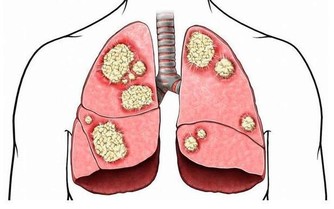

特別要說明的是,大腸癌也會導致慢性腹瀉。

不過一般來說,如果是因大腸癌導致的腹瀉,常常水性糞便中還混雜著血液,排便後還有糞便殘留的感覺,同時腹瀉與便秘交替、反復發生。

具體來說,大腸癌通常有以下症狀:便秘和腹瀉反復發生、有血便和便血、糞便很細、排便不爽、總感覺排便沒有排完全、腹部有腫塊、腹痛、有貧血症狀等等。